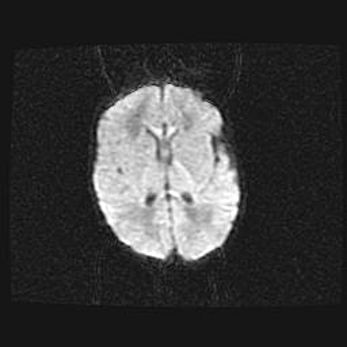

Церебральная ишемия II.

Возраст: 7 дней

Вес: 3350 г

Пол: женский

Окружность головы: 35 см

Срок гестации: 39 недель

Ишемия головного мозга – это состояние, которое развивается в ответ на кислородное голодание вследствие недостаточного мозгового кровообращения. У новорожденных она является следствием дефицита кислорода, что ведет к метаболическим расстройствам различной степени тяжести в тканях головного мозга, в том числе к развитию коагуляционных некрозов и гибели нейронов.